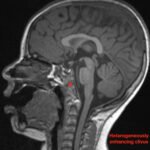

Pediatric neuroblastoma is famously characterized by an abdominal mass in a toddler with “raccoon eyes,” Horner syndrome, and/or opsoclonus myoclonus. However, rare cases may present with non-discrete symptoms and signs which create challenges for timely diagnosis. This case depicts a toddler with bulbar symptoms, including bilateral ptosis, dysphagia, drooling, head tilt and ataxia in a post-viral course mimicking other neurologic diagnoses, including myasthenia gravis. Magnetic resonance imaging (MRI) of the brain and spine uncovered a right adrenal mass along with heterogenous enhancement in multiple vertebral bodies and the clivus, consistent with metastatic disease. A diagnosis of neuroblastoma was confirmed with elevated homovanillic acid (HMA) and vanillylmandelic acid (VMA) levels and adrenal biopsy. The patient was treated with plasmapheresis for suspected paraneoplastic neurological syndrome and subsequent chemotherapy. In this case presentation, we review neurologic syndromes causing acute-onset pediatric bulbar weakness along with the patient’s key MRI findings.